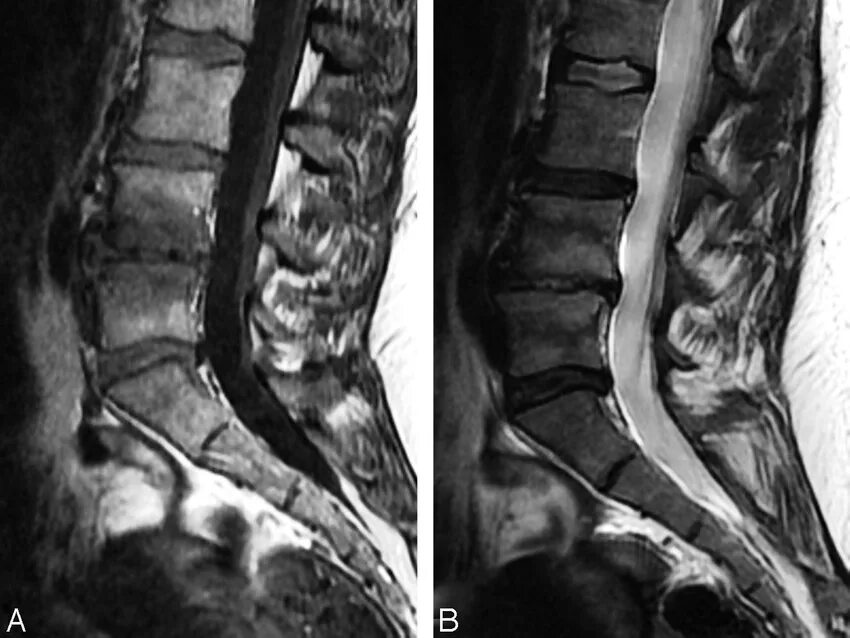

Modic тип 1